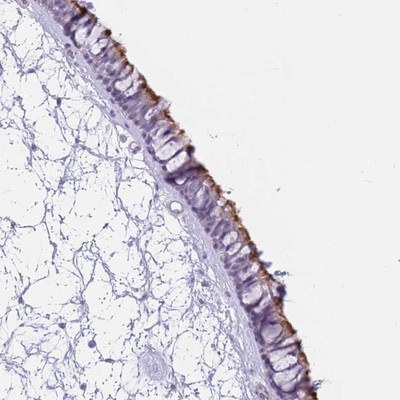

Supportive validation

- Submitted by

- Novus Biologicals (provider)

- Main image

- Experimental details

- Immunohistochemistry-Paraffin: ZNF239 Antibody [NBP1-92620] - Staining of human nasopharynx shows strong positivity in cilia of respiratory epithelial cells.